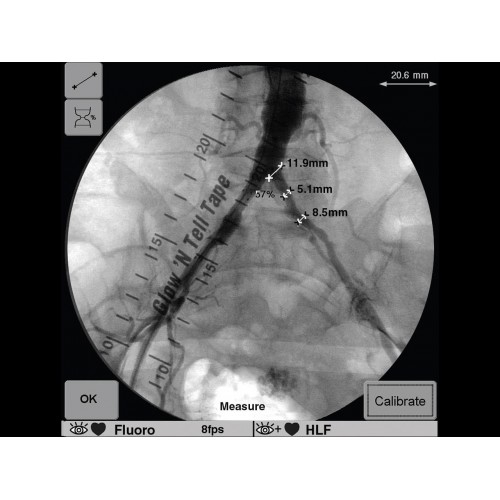

GE OEC 9900 Elite оснащен революционной системой визуализации, обеспечивающей кристально четкое изображение анатомических структур. Интеллектуальная система автоматически адаптирует параметры исследования под конкретную хирургическую задачу, обеспечивая оптимальный баланс между качеством изображения и лучевой нагрузкой. Особое внимание уделено удобству работы операционной бригады.

В операционной практике GE OEC 9900 Elite демонстрирует исключительную эффективность при проведении сложных малоинвазивных процедур. Оборудование позволяет значительно сократить время вмешательства и повысить его безопасность для пациента. Многие хирурги отмечают улучшение точности операций и комфорт работы с системой.